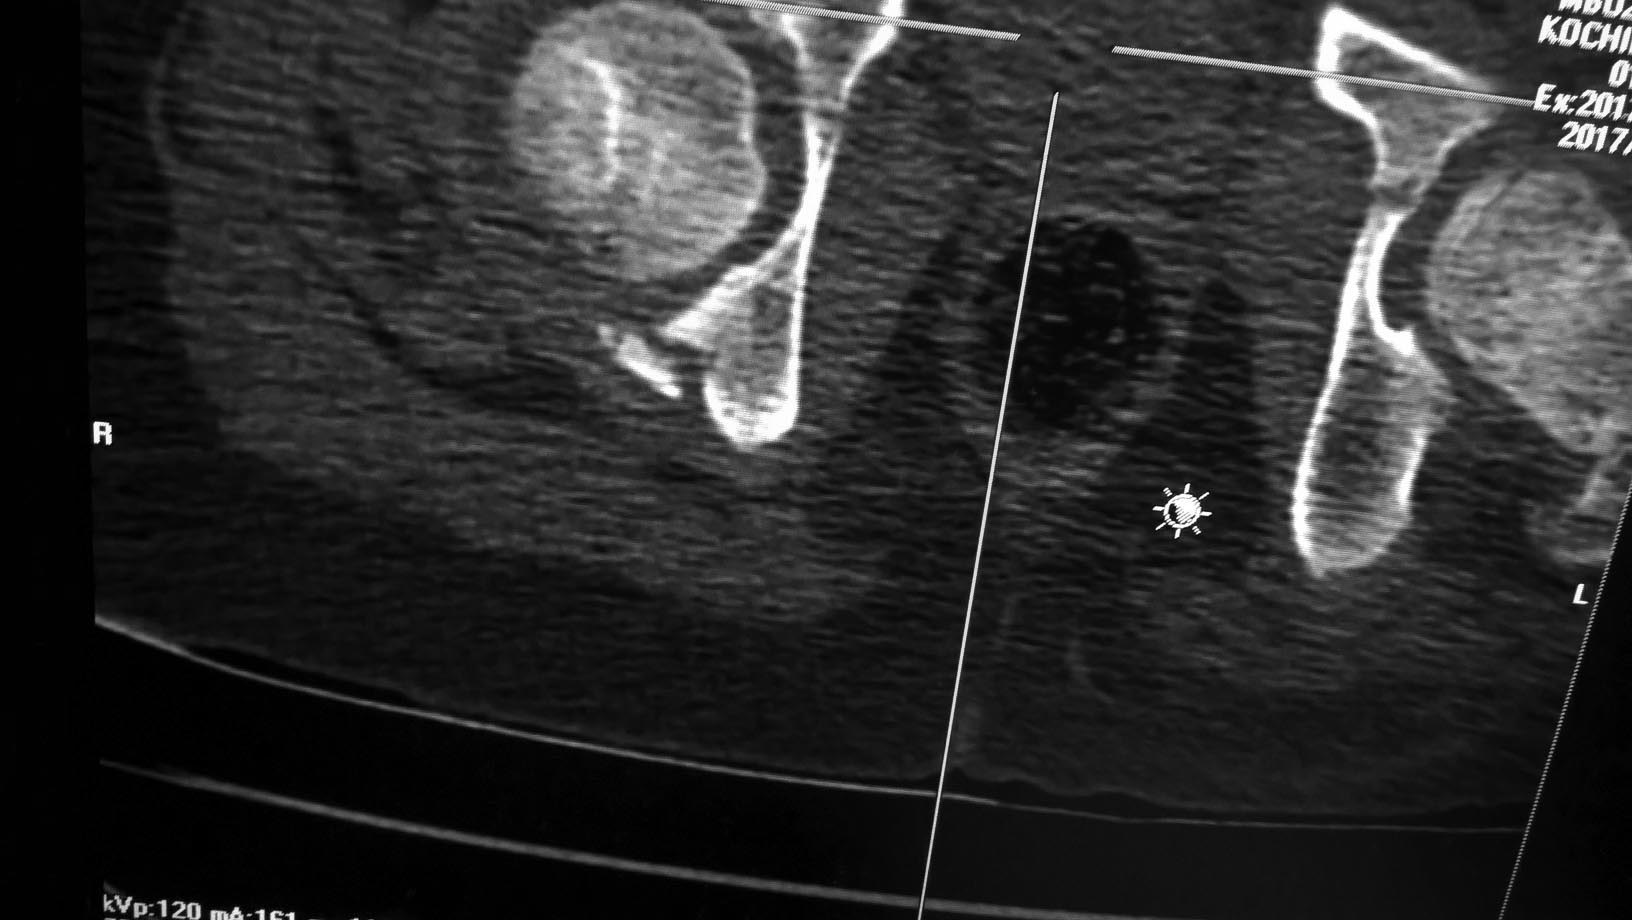

Ребенок 11 лет (мальчик), травма 04.07.17г: падение с высоты 3м. Вот

такой вот перелом вертлужной впадины. Есть ли необходимость в фиксации

перелома? Или будет достаточно 3 недели вытяжения, далее иммобилизация?